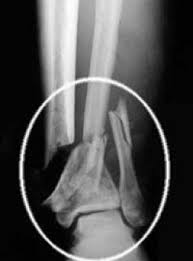

Stem Cells to Treat Broken Bones

The method, which is being hailed as a significant advancement in stem cell treatments for fractures and breaks, involves the isolation of multi-potent stem cells (or MSCs) which, broadly speaking, may be used as a universal healing cell, as they are capable of identifying and replicating the tissues that require replacement.

In the past the use of MSCs was limited due to the fact that the isolation and incubation process was a lengthy one, involving extensive laboratory hours to harvest the necessary cells for treatment. However, the Hebrew University researchers claim to have perfected a new form of cell recovery called immune isolation, which allows the cells to be harvested from the bone or fat of the patient and used immediately in a therapeutic fashion. The researchers concluded that the new method could greatly improve the prognosis of individuals with severe injuries including bone fractures and tendon tears.